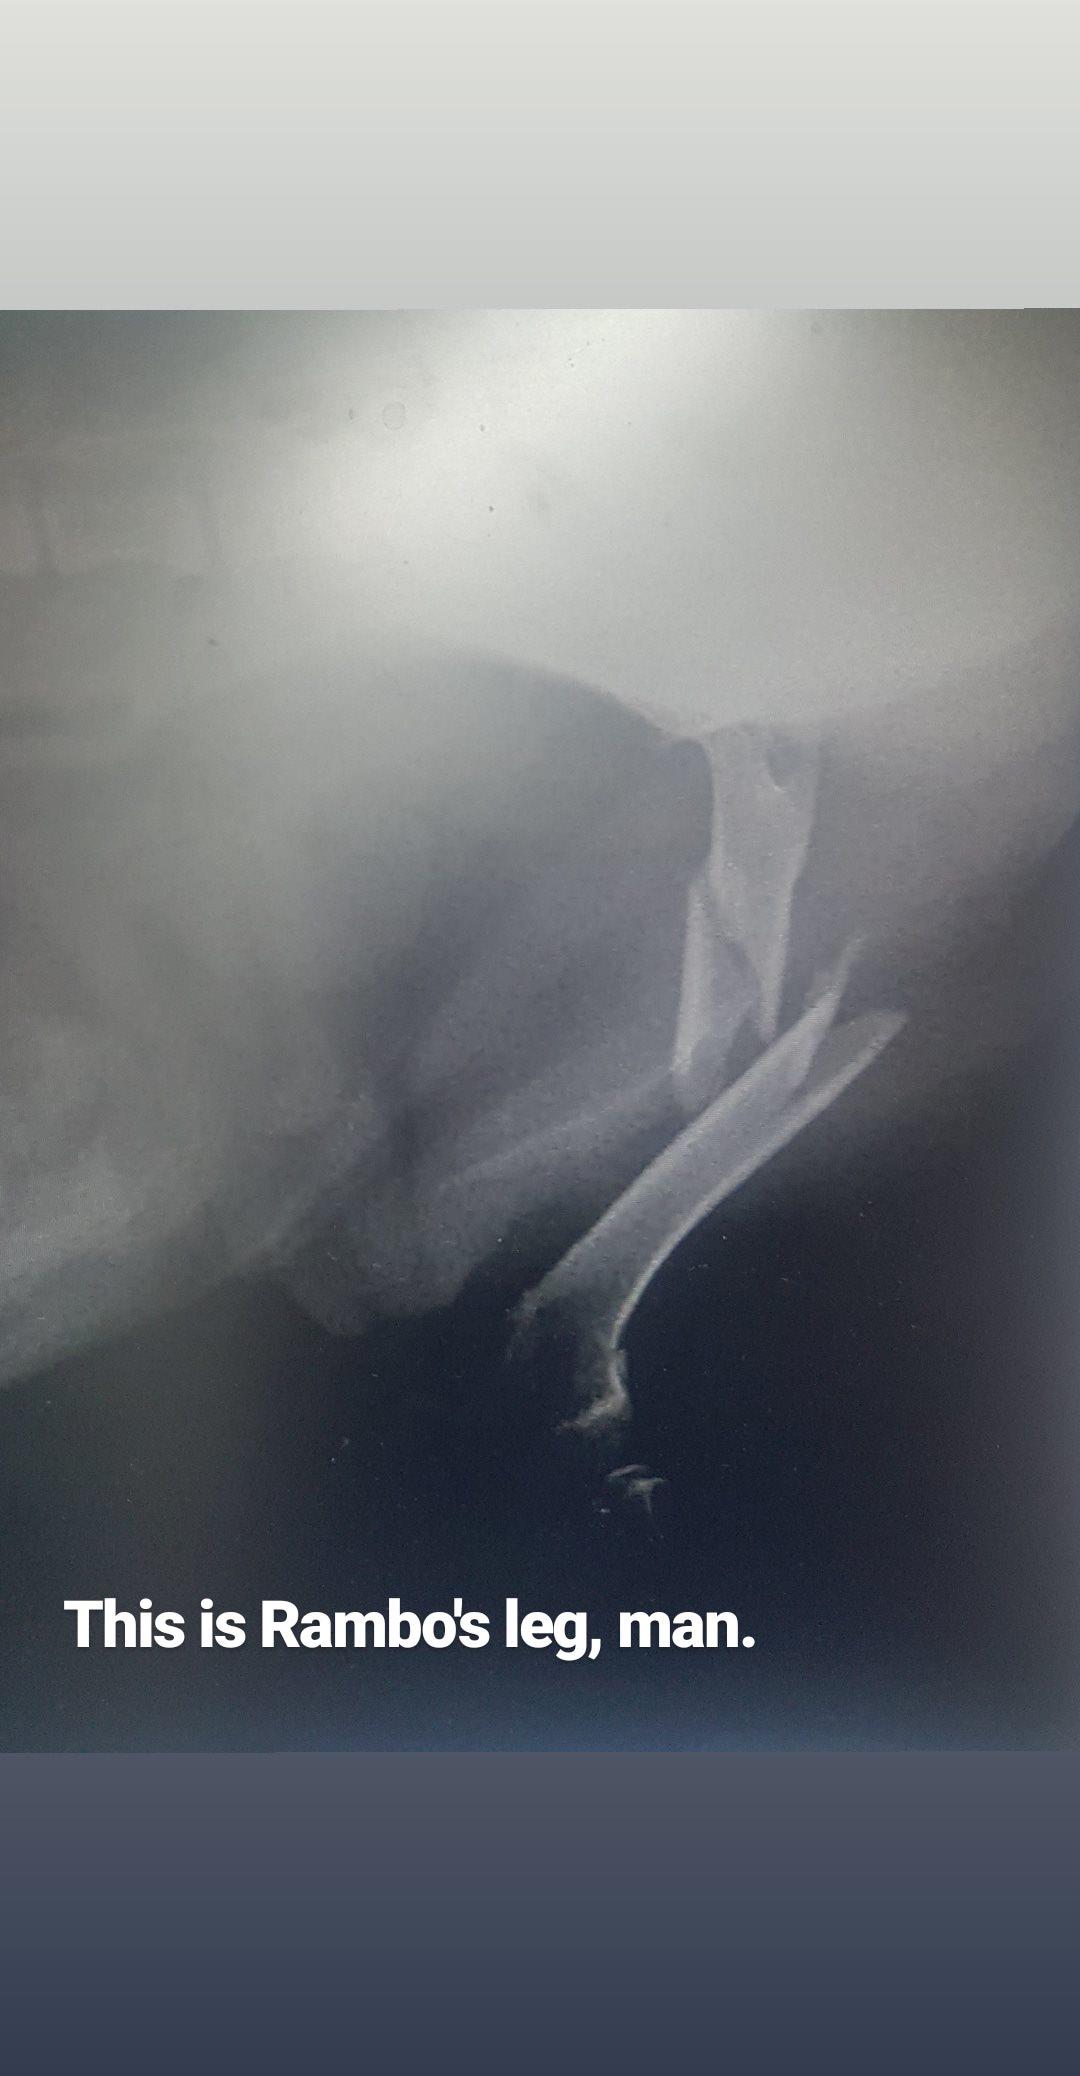

• Rambo's staying at the Vets overnight

Main image

They're going to attempt to put a pin into place to help the bones heal together. This will cost about $1000-$2000 just for the surgery not including further xrays or costs that crop up from possible complications. But we hope and pray it goes smoothly. Thanks so much for those that have already donated and shared. Angels, all of you. Love from us and Rambo x